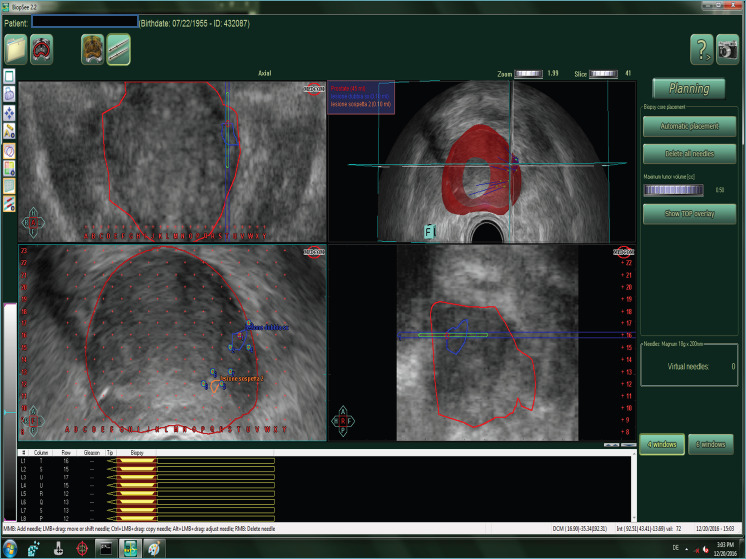

Multiparametric magnetic resonance imaging (mpMRI) has improved systematic prostate biopsy procedures in the diagnosis of clinically significant prostate cancer (csPCa) by reducing the number of unnecessary biopsies; numerous level one evidence studies have confirmed the accuracy of MRI-targeted biopsy, but, still today, systematic prostate biopsy is recommended to reduce the 15-20% false negative rate of mpMRI. New advanced imaging has been proposed to detect suspicious lesions and perform targeted biopsies especially when mpMRI cannot be performed. Transrectal ultrasound (TRUS) modalities are emerging as methods with greater sensitivity and specificity for the detection of PCa compared to the traditional TRUS; these techniques include elastography and contrast-enhanced ultrasound, as well as improved B-mode and Doppler techniques. These modalities can be combined to define a novel ultrasound approach: multiparametric ultrasound (mpUS). More recently, micro-ultrasound (MicroUS) and prostate-specific membrane antigen (PSMA) positron emission tomography/computed tomography (PET/CT) have demonstrated to be sensitive for the detection of primary prostatic lesions resulting highly correlated with the aggressiveness of the primary prostatic tumor. In parallel, artificial intelligence is advancing and is set out to deeply change both radiology and pathology. In this study we address the role, advantages and shortcomings of novel imaging techniques for Pca, and discuss future directions including the applications of artificial intelligence-based techniques to imaging as well as histology. The significance of these findings for the practicing pathologist is discussed.

Abstract Image